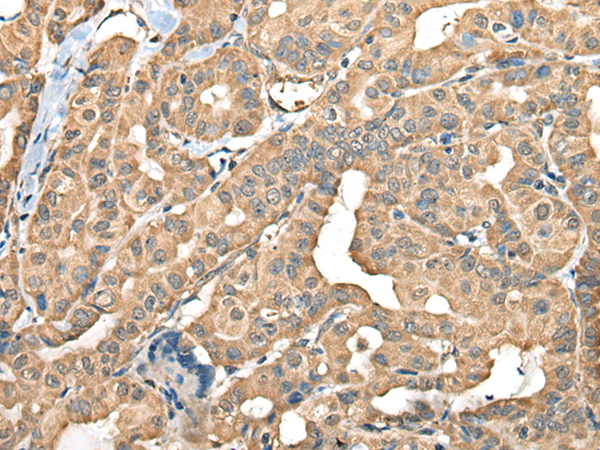

IHC positive control: |

Human thyroid cancer |

IHC Recommend dilution: |

40-200 |